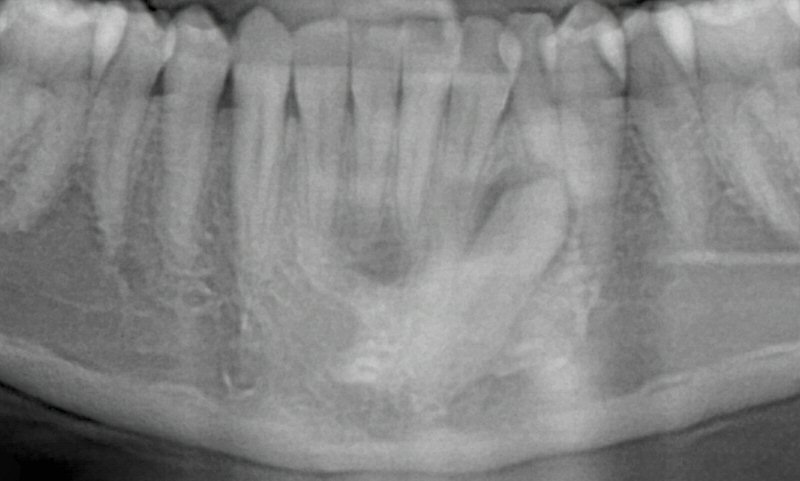

The status of the impacted lower left canine (before orthodontic treatment) are shown in Figs. 13 & 14.

Fig. 13 Initial panoramic radiograph (cropped) of impacted lower left canine (at 16 y.o.)

© Copyright 2007-2014, Vu Orthodontics. All rights reserved.